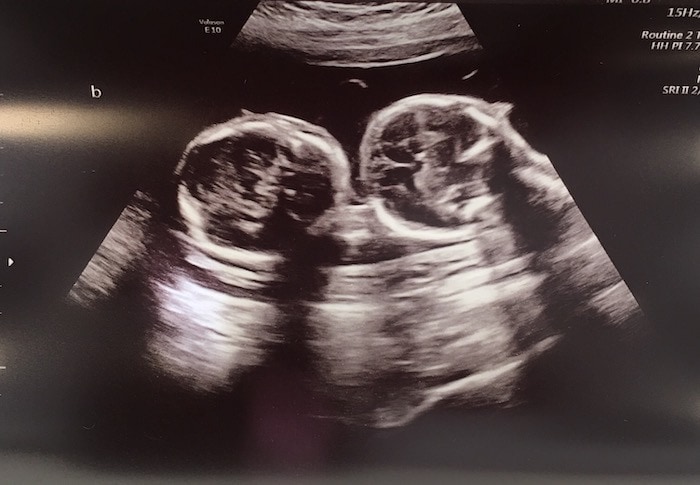

Ultrasound Photos at 21 Weeks Pregnant With Twins